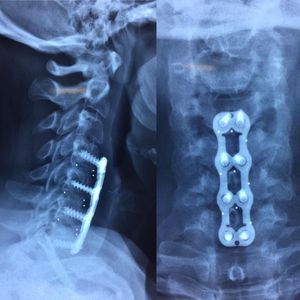

FUSION FUSION FUSION !!!This is one of the first operations that i was in the operating room for. ACDF or anterior cervical dissection and fusion is an operation that is used when herniated disc is impacting roots of the spinal cord which can lead to severe nerve pain and tingling sensations on a patient. The surgeon will remove the herniated disc completely and replace it with a cervical cage that is packed with either artificial bone graft or harvested bone such as osteophytes, or a combination of both. The surgeon will then use a plate the stabilize the levels of the vertebra depending on the severity of the case. cervical plates can come in different levels to fuse different layers at the same time. C4,C5 C5,C6 C6,C7 Screws inserted. The downside to a fusion with this many levels is that mobility will be decreased.